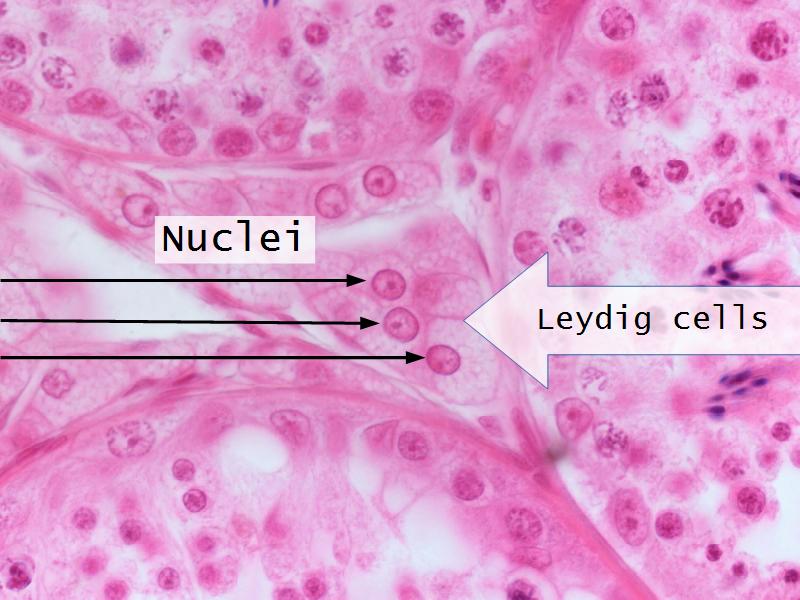

- D1: Leydig cells

- D1: Leydig cells = testosterone